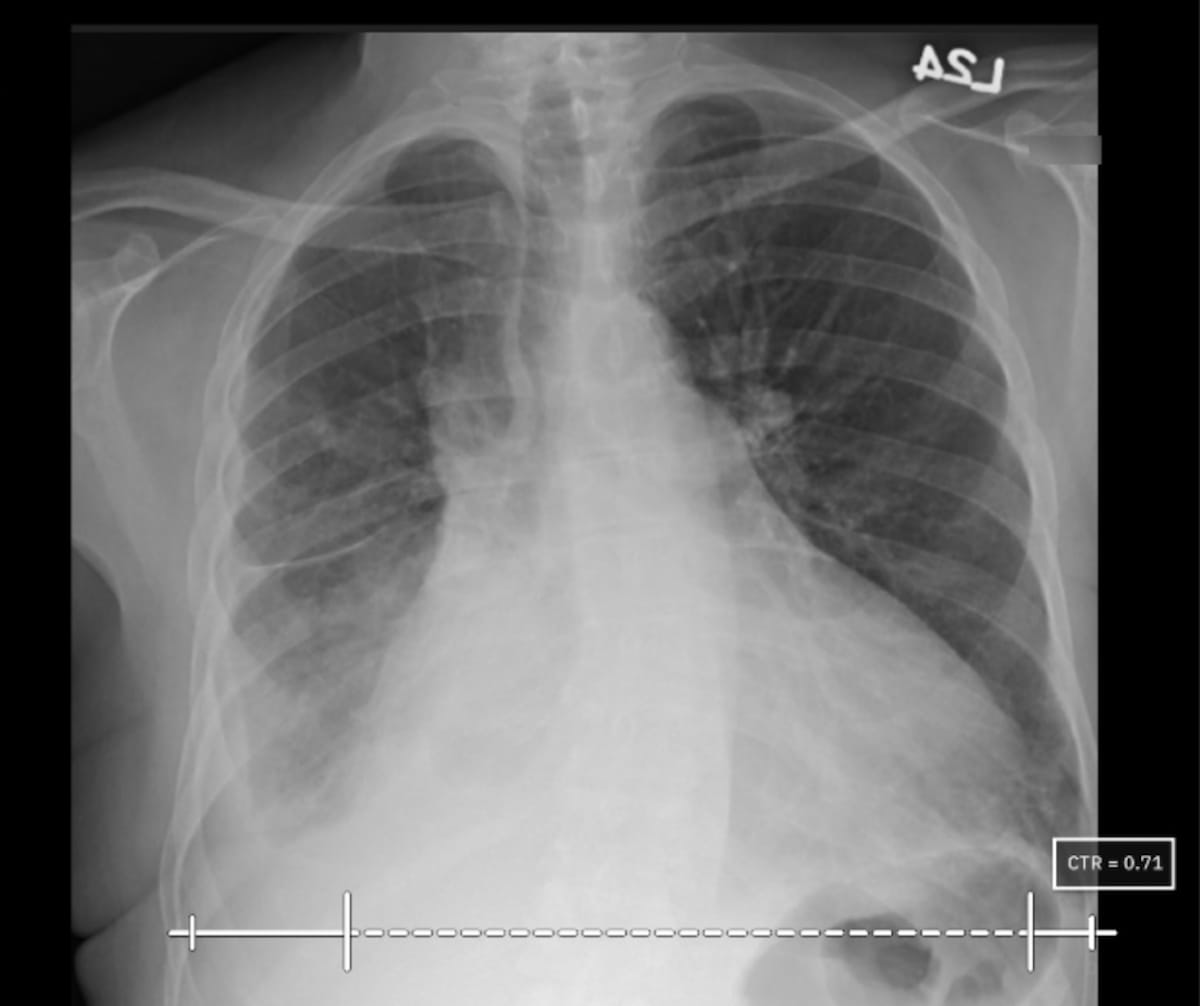

In a multicenter study examining four commercially available artificial intelligence (AI) software products for chest X-rays in over 2,000 patients, researchers found sensitivity rates ranging between 33 to 61 percent for vague airspace disease and 9 to 94 percent for small pneumothorax and pleural effusion.